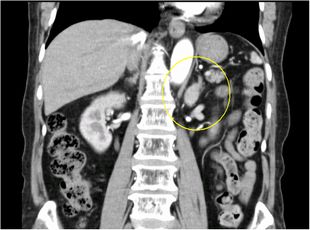

超音波検査、CT検査で副腎腫瘍を認めた場合、血液検査・尿検査などでホルモンを過剰に産生していないかを調べます。

必要に応じてMRI検査や血管造影検査(左右の副腎静脈からホルモンサンプリング)を追加して総合的に診断します。